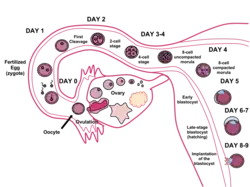

Беременность возникает в результате слияния женской и мужской половых клеток в маточной трубе, после чего происходит образование зиготы, содержащей 46 хромосом. Пол будущего ребёнка зависит от набора половых хромосом (XX или XY), при этом яйцеклетки всегда являются носителями X-хромосомы, а сперматозоиды — X- или Y-хромосомы (в соотношении 1:1). Таким образом, пол будущего ребёнка определяется именно половой хромосомой, носителем которой является сперматозоид (в случае X-хромосомы — родится ребёнок женского пола, а в случае Y-хромосомы — мужского)[5]. Однако существуют исключения из этого правила — интерсекс-вариации. В результате деления клеток образуется бластоциста, которая на седьмые сутки прикрепляется к стенке матки. В первые три месяца беременности (первый триместр) закладываются органы плода, к концу 12-й недели полностью оформляется плацента. Через неё плод получает питательные вещества и происходит удаление конечных продуктов обмена.

Внутриутробное развитие человека принято разделять на периоды. Развитие эмбриона от оплодотворения яйцеклетки до начала имплантации (первая неделя развития) характеризуют как преимплантационный период (см. Зачатие у человека), последующее развитие относят к постимплантационному периоду. В преимплантационный период эмбрион не прикреплён к стенке матки матери, в течение первых 4 дней эмбрион движется от места оплодотворения (ампулярная часть маточной трубы) по фаллопиевой трубе в сторону матки, на 5-6 день развития эмбрион находится в матке женщины подготавливая себя к имплантации (см. Zona pellucida). Также принято выделять эмбриональный (первые 8 недель от оплодотворения) и фетальный (от 9 недели до родов) периоды развития. В течение эмбрионального периода происходит пространственная организация первичных структур (морфогенез), начальная дифференцировка клеток и закладка систем органов (органогенез). В течение фетального периода происходит развитие органов в рамках сформированных систем, в значительной степени происходит увеличение размеров плода.

Эмбриональный период

Эмбриональный период длится от момента оплодотворения до конца 8 недели эмбрионального срока (10 неделя акушерского срока). В течение эмбрионального периода происходит эмбриогенез, в частности, такие процессы, как оплодотворение, дробление (образование многоклеточности), имплантация (внедрение в матку), гаструляция (образование зародышевых листков), гистогенез (формирование тканей), органогенез (формирование органов), плацентация и прочие процессы. В течение эмбрионального периода зародыш увеличивается в размере с 0,1 мм (оплодотворённая яйцеклетка) до 3 см (без учёта плодных оболочек). Изначально зародыш не напоминает младенца и лишь постепенно он приобретает черты и строение, сходные с младенцем. На последней неделе эмбрионального срока у эмбриона исчезают некоторые эмбриональные структуры (жаберные дуги и жаберные щели, хвост, уменьшается аллантоис).